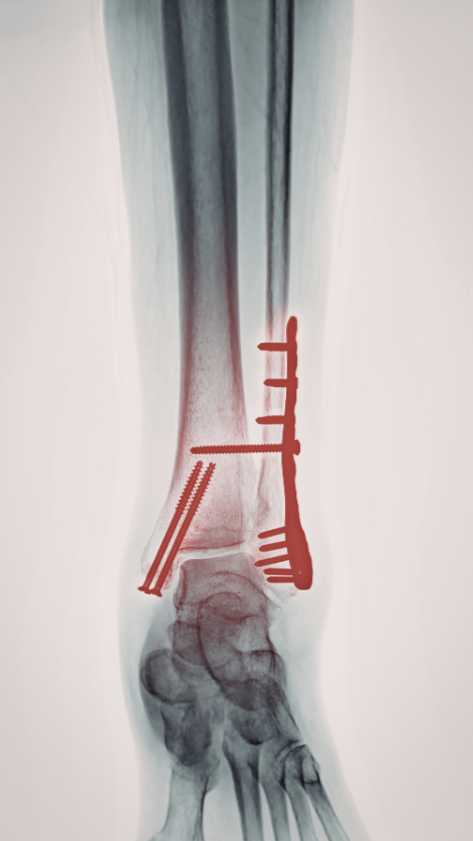

Tratamiento de fracturas y edemas óseos

Enfrentar una fractura o un edema óseo no es solo un diagnóstico médico; es una interrupción en tu vida diaria, en tu proyectos deportivos y laborales y en tu bienestar. El dolor persistente y la incertidumbre de una recuperación lenta pueden ser agotadores.

El éxito de la magnetoterapia en el ámbito de la traumatología y la medicina deportiva reside en su capacidad de modular la respuesta biológica del hueso. Ante una fractura, el hueso requiere un entorno metabólico óptimo para formar el "callo óseo".